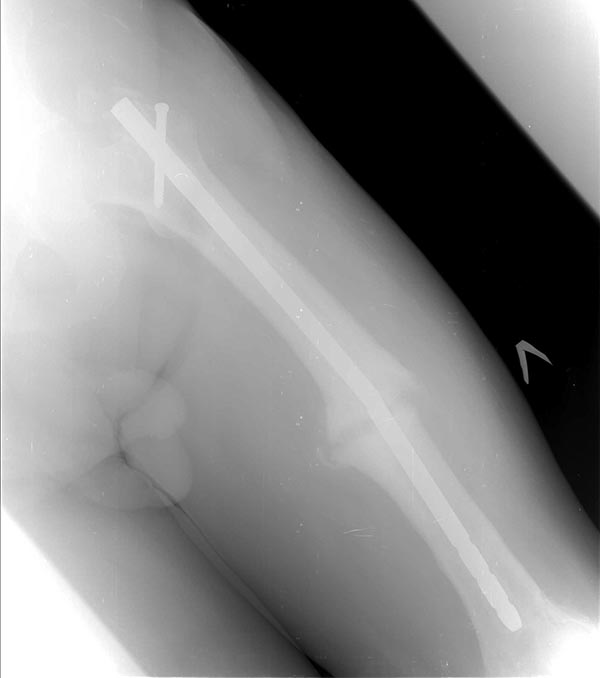

Коротко о пациенте: Возраст 60 лет, мужчина. Со слов травма в 2006

года-ДТП (сбит автомашиной) - в январе 2007 г. выполнено БИОС левого

бедра , затем по неизвестным причинам в 2008 году реостеосинтез левого

бедра штифтом ( снимков нет). Оперирован в одном из городов Сибири.

На снимках( это снимки январь 2015г), которые выложил, определяется

гипертрофический ложный сустав с/3 бедренной кости, перелом штифта на

уровне перелома, штифт канюлированный.Состояние больного